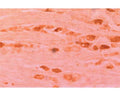

Anti-Neurturin (NTN) Antibody

Our Anti-Neurturin (NTN) rabbit polyclonal primary antibody detects human, mouse, and rat Neurturin (NTN), and is whole serum. It is validated for use in IHC-Frozen.